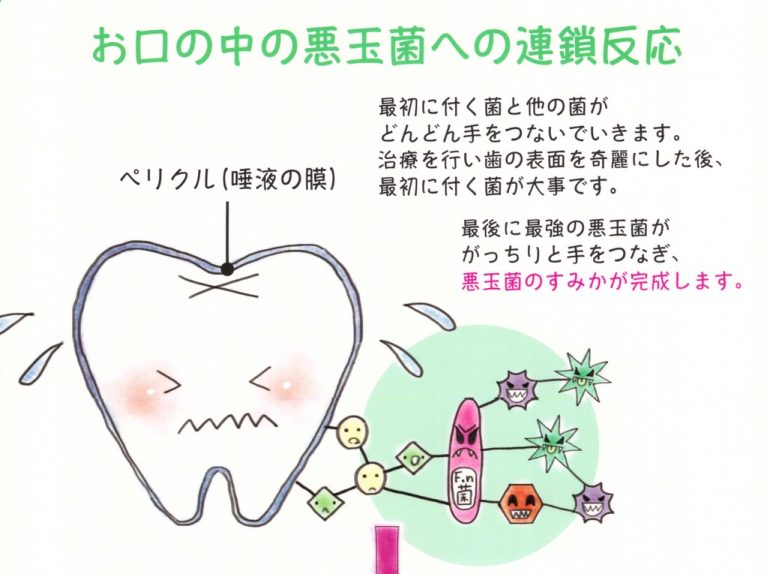

市販の歯磨き粉には薬品の成分ですっきり感じるようにしたり、歯磨剤が入り歯の表面を細かく傷が入り磨いているのにプラークや細菌が歯の表面に付着しやすくなります。磨いているのに、虫歯になってしまうのは歯の表面に付着する虫歯菌が取れていないためです。

薬品成分の殺菌剤が含まれている歯磨き粉で磨くとお口の中の善玉菌も殺菌されるため、善玉菌と悪玉菌のバランスが崩れ、逆に悪玉菌が活発に活動してしまうことも・・・

※歯に影響する悪玉菌とは虫歯菌と歯周病菌のことです

口腔内環境は常に正常な状態に保ち、善玉菌が優位な状況を作ることが大切です